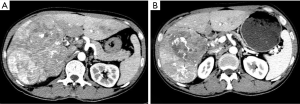

No patient in either treatment group had a CR according to mRECIST (Table 2). In total, 5 (19.2%) patients in the apatinib group versus 1 (2.2%) patient in the sorafenib group had a PR (P=0.012); 10 (38.5%) patients in the apatinib group versus 22 (47.8%) patients in the sorafenib group had a SD (P=0.442); 11 (42.3%) patients in the apatinib group versus 23 (50%) patients in the sorafenib group had a PD (P=0.530); and 15 (57.7%) patients in the apatinib group and 23 (50%) patients in the sorafenib group achieved disease control (P=0.530). (Representative images in Figures 2 and 3).